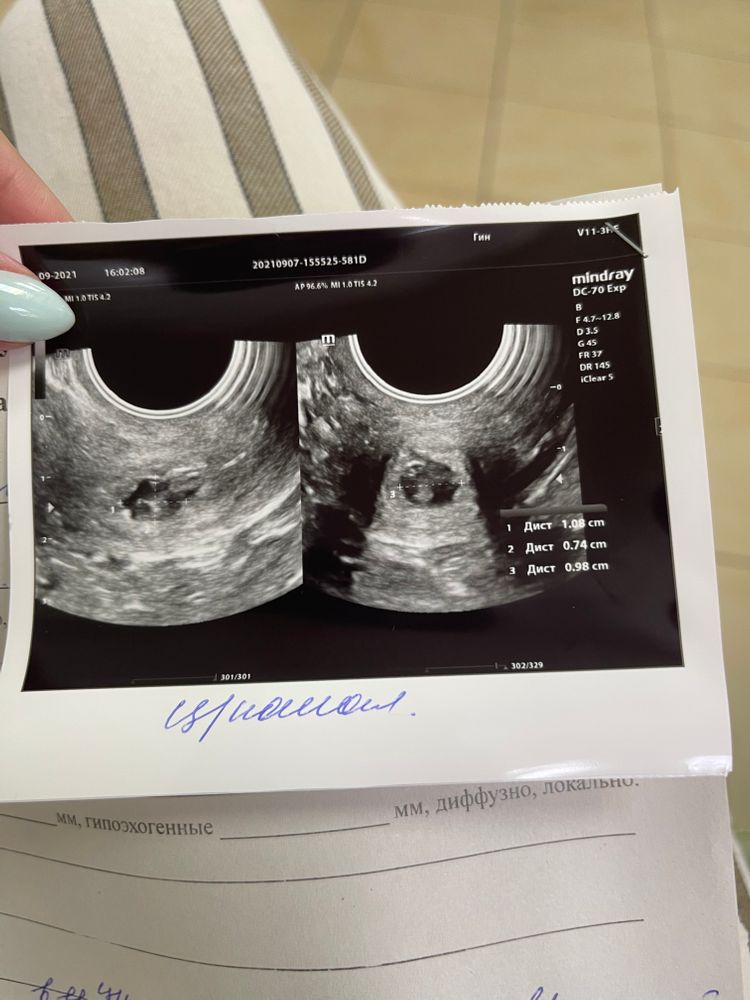

Всем привет, сейчас на дневном стационаре в ЖК, ставят это диагноз с подозрением на воспаление. На ужи есть киста жт и образование в цервикальном канале 1 см. Тянет низ живота .Приложу фото узи.

Что это? Киста? Полип? Только взяли онко, который будет готов через 3 недели и ничег не сказали